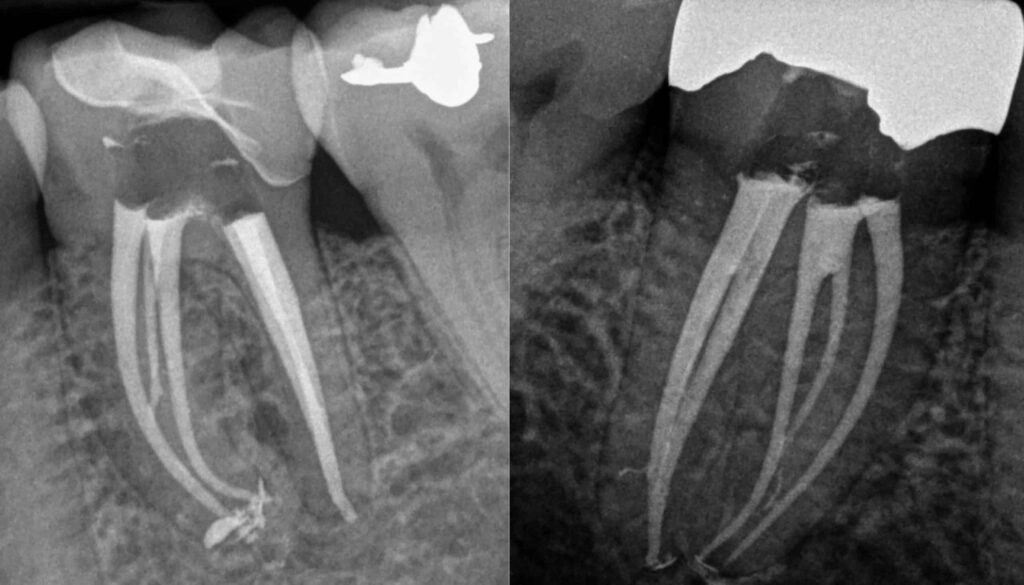

Ένας συχνός λόγος επίσκεψης σε ενδοδοντολόγο είναι η επανάληψη μιας ενδοδοντικής θεραπείας που έχει γίνει από κάποιον άλλον λιγότερο εξειδικευμένο συνάδελφο.Πρέπει να διευκρυνιστεί πως κάθε ατελής θεραπεία που έχει πραγματοποιηθεί δεν χρήζει επανάληψης. Άλλο ατελής θεραπεία και άλλο αποτυχημένη θεραπεία.Στο ιατρείο μας αναλαμβάνουμε μόνο περιστατικά με αποτυχημένες θεραπείες που έχουν δημιουργήσει πρόβλημα και συστήνουμε μόνο παρακολούθηση των περιστατικών με ατελείς θεραπείες.Η φιλοσοφία μας είναι της ελάχιστης παρέμβασης και σε κάθε ασθενή κοιτάμε αν μπορεί να γλυτώσει μια άσκοπη θεραπεία από εμάς.

Πρέπει επιπλέον να αναφερθούμε στο γεγονός πως η ενδοδοντολογία είναι ίσως η πιο άδικημένη ειδικότητα της οδοντιατρικής. Είναι ο πόλεμος ενάντια στη μόλυνση των δοντιών.Σε αντίθεση με τις άλλες ειδικότητες που το αποτέλεσμα είναι άμεσα ορατό (πχ. όπως στην εξαγωγή ενός δοντιού ή στην τοποθέτηση μιας έμφραξης) στην ενδοδοντική θεραπεία δεν μπορούμε να δούμε με το μάτι ούτε να ξέρουμε πόσα και ποια μικρόβια αφαιρέσαμε. Μπορούμε να επιτύχουμε μερική απολύμανση και όχι πλήρη αποστείρωση του δοντιού.Αυτό καθιστά την αποτελεσματικότητα επισφαλή σε περιστατικά με έντονες λοιμώξεις ή σε δόντια με εξωρριζικές μολύνσεις τα οποία χρειάζονται συχνά περιακρορριζική χειρουργική.Όλα αυτά πρέπει να γίνουν κατανοητά και να εξηγούνται πριν από τη θεραπεία κάθε περιστατικού ώστε ο υποψήφιος ασθενής να γνωρίζει ότι υπάρχει το ενδεχόμενο αποτυχίας ακόμα και στα χέρια του καλύτερου ιατρού.